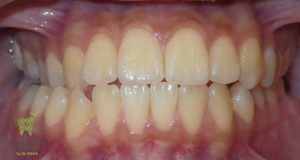

Surgical case of midline discrepancy and class III malocclusion treated non-surgically. Patient was thrilled to achieve excellent results without surgery.